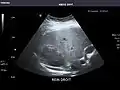

Liver

Ultrasonography of the liver with some standard measurements[6]

In patients with deranged liver function tests, ultrasound may show increased liver size (hepatomegaly), increased reflectiveness (which might, for example, indicate cholestasis), gallbladder or bile duct diseases, or a tumor in the liver.

Ultrasonography of liver tumors involves two stages: detection and characterization. Tumor detection is based on the performance of the method and should include morphometric information (three axes dimensions, volume) and topographic information (number, location specifying liver segment and lobe/lobes). The specification of these data is important for staging liver tumors and prognosis. Tumor characterization is a complex process based on a sum of criteria leading towards tumor nature definition. Often, other diagnostic procedures, especially interventional ones, are no longer necessary. Tumor characterization using the ultrasound method will be based on the following elements: consistency (solid, liquid, mixed), echogenicity, structure appearance (homogeneous or heterogeneous), delineation from adjacent liver parenchyma (capsular, imprecise), elasticity, posterior acoustic enhancement effect, the relation with neighboring organs or structures (displacement, invasion), vasculature (presence and characteristics on Doppler ultrasonography and contrast-enhanced ultrasound (CEUS).